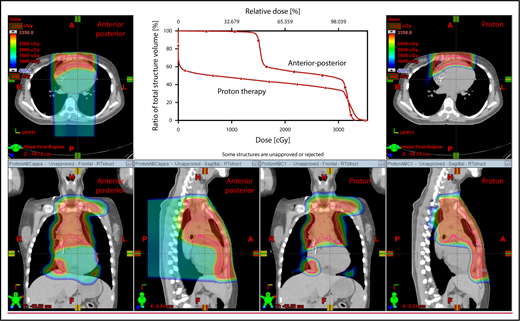

The plan target is the CTV; when the treatment area is affected by breathing motion, the plan target is the internal target volume (ITV), which encompasses the motion of the CTV depicted on 4D CT scans. Alternately, if treatment is to be given with DIBH, an ITV can be derived from the positions of the CTV reproduced from multiple DIBH scans. For lateral beam shaping, margin expansion to form the PTV accounts for setup uncertainty, and interfractional variability in anatomy is applied to the CTV/ITV. Patient-specific beam collimators conform the dose laterally to the PTV, with a margin for penumbra. Depending on the target depth and adjacent tissue, these margins vary from 5 to 10 mm. Range compensators are designed for each beam to conform the dose distally to the CTV/ITV. Range compensator smearing within a radius appropriate for setup tolerances and tissue motion is applied to account for proton range changes caused by density changes in the beam path. In addition, along each beam, distal and proximal margins are set to the CTV/ITV to compensate for proton range uncertainties, as described under “Range uncertainties due to density variations.” Multiple beams (compared with 1 beam) can be used to increase dose conformality and reduce dose uncertainties by spreading the beams in various directions. The preference is to use anterior or posterior fields, rather than both, because of the need to avoid unnecessary beam through the heart (Figure 4).

An example of an approach using 2 anterior fields with proton therapy, which can better spare the heart and esophagus (right) compared with an anterior/posterior approach (left).

With regard to field arrangements, the PBSPT technique for an anterior upper mediastinal and lower neck target usually requires 1 (repainted) or 2 anterior fields. For more complex target volumes, targets can be divided into 2 or more parts (eg, neck CTV, mediastinal CTV, and axillary CTV), and a multifield plan can be used (Figure 5). For cases that involve lower (posterior) and upper (anterior) mediastinal targets, a combination of posterior and anterior fields can maximally spare the heart and lungs (Figure 6). For upper neck targets, lateral or posterior fields can avoid the oral cavity/salivary structures. For axillary targets, a posterior field can help to spare breast tissue. Although these various field arrangements can be used in PSPT, gradient matching is simpler in PBSPT when the fields overlap or oppose, obviating the need for feathering.

Plans for PBSPT with a single-field uniform dose and a gradient match, with anterior and posterior beams used to treat disease that involves the bilateral upper neck and the mediastinum (disease anterior to the right heart).

Scans for a young woman in whom the target included mediastinal, left parasternal, and left axillary regions. One anterior field was used for the mediastinum, and a separate posterior field was used for the axillary region.